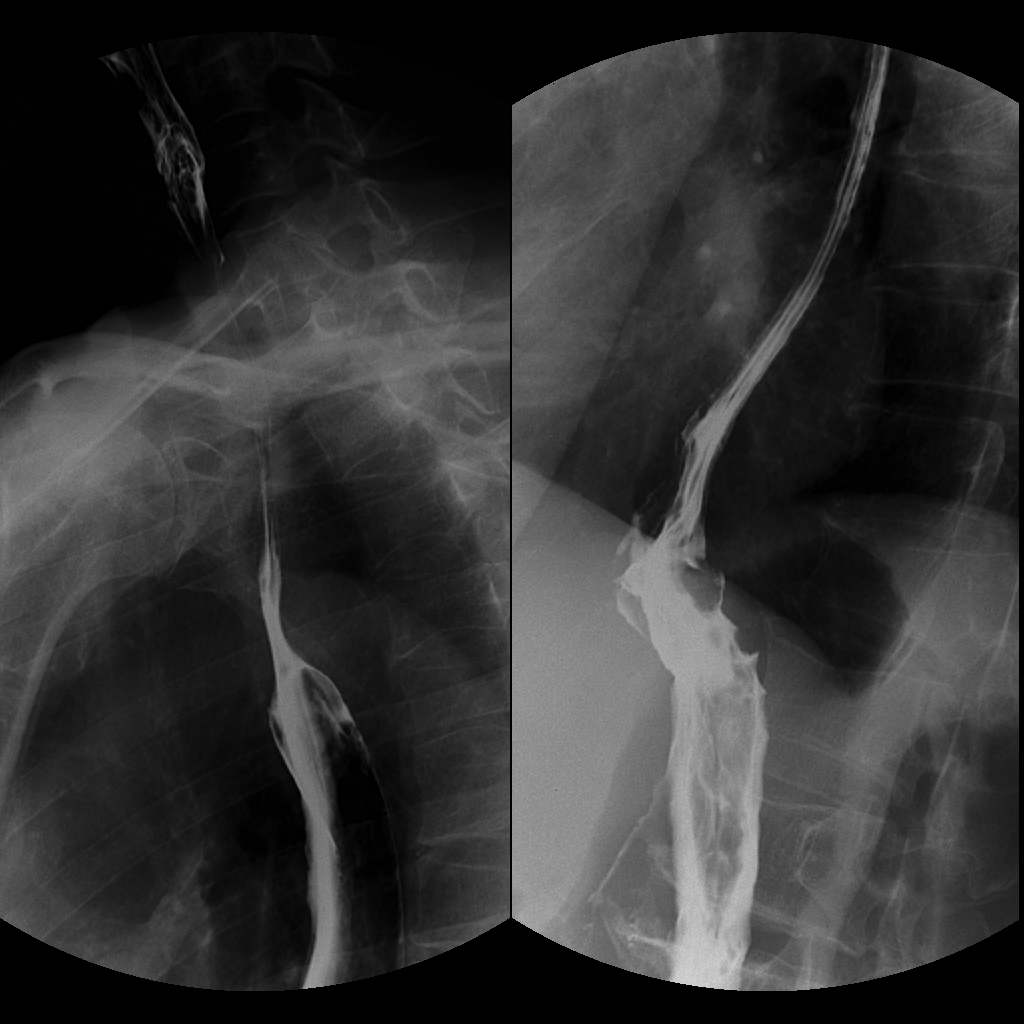

患者因进食梗噎1月余就诊于当地医院,行胃镜检查发现食管胃结合部粘膜弥漫性病变。由于病变时间较长,患者迫切地想要获得症状改善,转入我院胸外科。来院后复查电子胃镜示:腹段食管、贲门、胃底、胃体粘膜弥漫性粘膜粗糙、增厚、僵硬,局部粘膜中断。胃镜病理示:低分化癌。消化道钡透示:食管远端、贲门结构不清,胃底、胃体僵硬,管腔狭窄,考虑恶性肿瘤浸润。超声内镜及胸腹部增强CT未提示肿瘤侵及临近器官及远处转移。

术前上消化道钡透示食管远端、贲门结构不清,胃底、胃体僵硬,管腔狭窄,考虑恶性肿瘤浸润